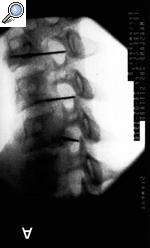

Con el paciente en decúbito supino y el cuello en ligera hiperextensión, se realizan 4 movimientos con el arco de rayos (Rx). Con el Rx en posición lateral, se identifica el nivel que se va a tratar. Cuando se ha identificado, se realiza un movimiento del Rx en posición oblicua hasta que se visualiza el foramen completamente). Cuando el foramen se ve claramente, se realiza un movimiento craneocaudal para eliminar el doble contorno del agujero que se va a tratar. Por último, con una proyección anteroposterior, se debe visualizar la punta de la aguja en la porción media de la articulación facetaria.

Figura 1. A: proyección oblicua de la columna cervical en la que se puede ver que la aguja se dirige a la parte posterior del foramen. B: proyección anteroposterior donde se aprecia que la aguja sobrepasa la línea facetaria.

Anatómicamente, se debe tener en cuenta que la arteria vertebral ocupa la parte anterior del agujero de conjunción, por lo que es de suma importancia, para evitar complicaciones nefastas4,5, el acercamiento en la parte posterior; asimismo es importante saber que el primer agujero que se visualiza es el que corresponde a C3 y, por último, que en la zona cervical la raíz sale por encima del cuerpo vertebral correspondiente (la raíz C4 sale entre C3 y C4). El punto diana es la porción inferior del agujero radicular, ya que el ganglio dorsal de la raíz se localiza en la unión de los tercios medio e inferior del foramen.